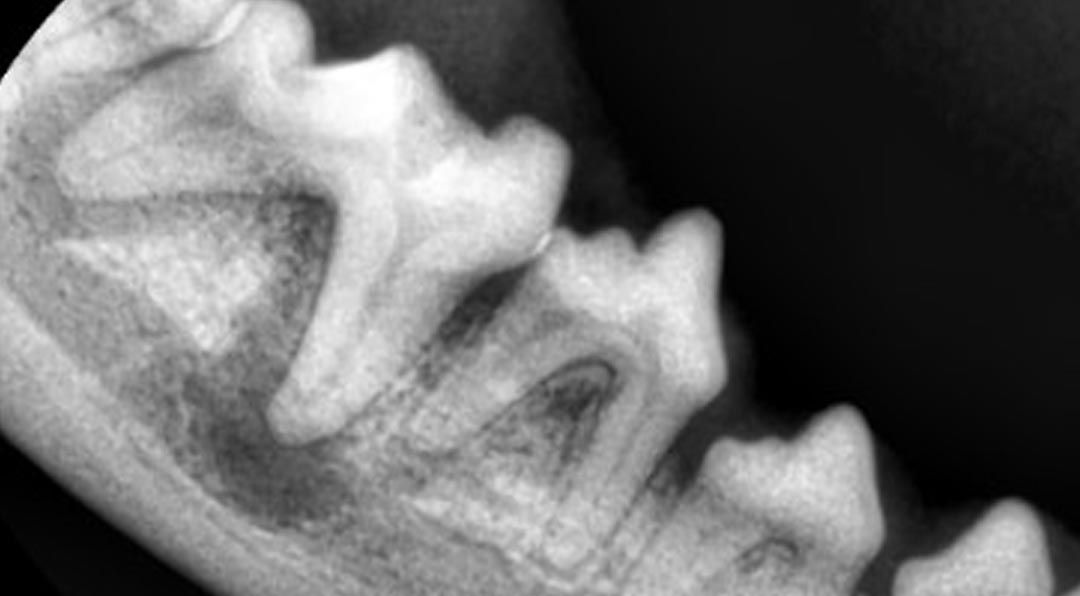

치과 클리닉은 반려동물의 치아, 치주조직, 구강점막 등 구강 전반의 건강을 진단하고 치료하는 전문 진료과입니다. 강아지와 고양이 모두 3세 이상이 되면 약 80% 이상이 치주 질환을 경험하게 되며, 이는 전신 질환으로도 이어질 수 있어 정기적인 치과 진료가 매우 중요합니다. 치과 클리닉에서는 스케일링, 발치, 치주수술, 교합 이상, 턱뼈 문제까지 종합적인 진료를 제공합니다.

플라그와 치석으로 인해 잇몸에 염증이 생기고, 점차 치조골까지 손상이 진행되는 만성 질환입니다. 방치할 경우 치아가 흔들리거나 빠지게 되고, 세균이 혈류를 타고 심장·신장 등 주요 장기에 영향을 줄 수 있습니다.

| 주요 질환 | 초기 치은염, 진행성 치주염, 치조골 흡수 |